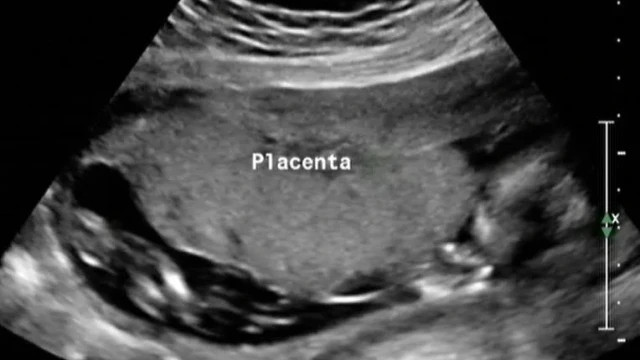

The placenta-on-a-chip model was fabricated and meticulously tested to simulate the transport of NTX/6β-naltrexol from the maternal channel to the fetal channel. From the fetal channel, the transported NTX/6β-naltrexol was collected and directed toward cultured N27 neural cells. The neural cells were then evaluated for gene expression and cell viability following exposure to the pharmaceutical agents.

By utilizing advanced liquid chromatography/mass spectrometry (LC-MS), the study effectively analyzed the transport of clinically relevant concentrations of NTX and 6β-naltrexol.